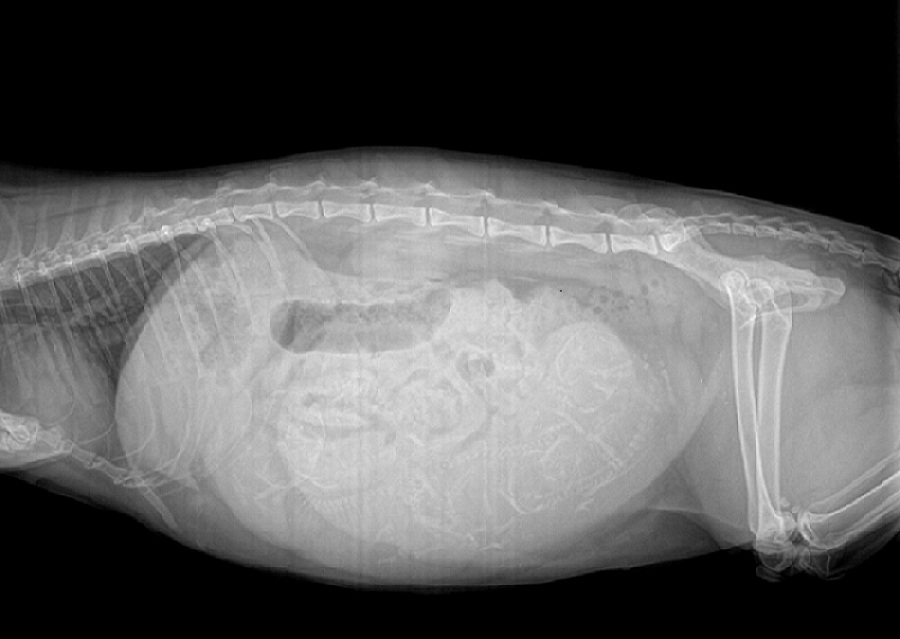

小公主X光

各位大大覺得我們小公主他到底肚子裡面有幾隻呢?

目前我看到的應該有5隻....

難怪那顆肚子又大又圓.....

要請獸醫幫忙量一下小公主X片光

小公主的產道寬度是否大於小貓ㄉ頭圍寬度

一般母貓產道都 要大於小貓ㄉ頭圍寬度唷~~